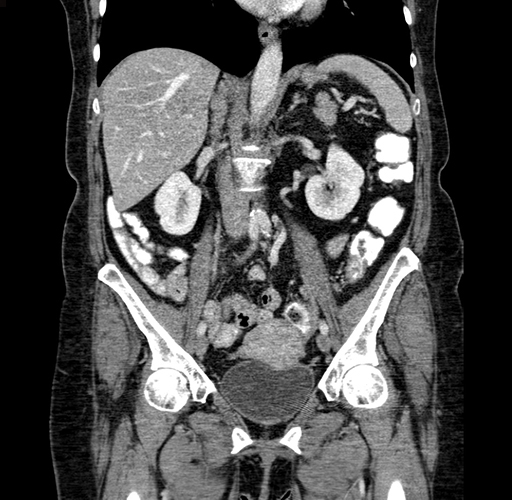

Pre-Chemo: Coronal Venous

Coronal Venous